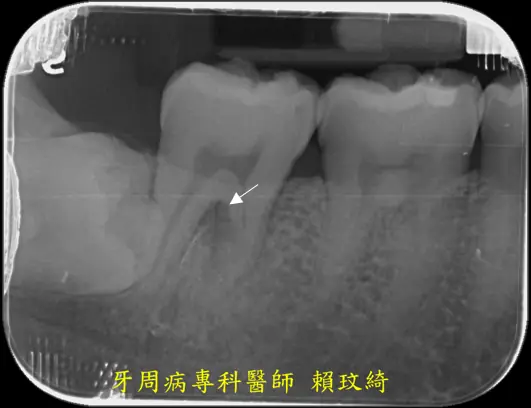

牙周再生手術+牙根覆蓋術

治療前

治療後